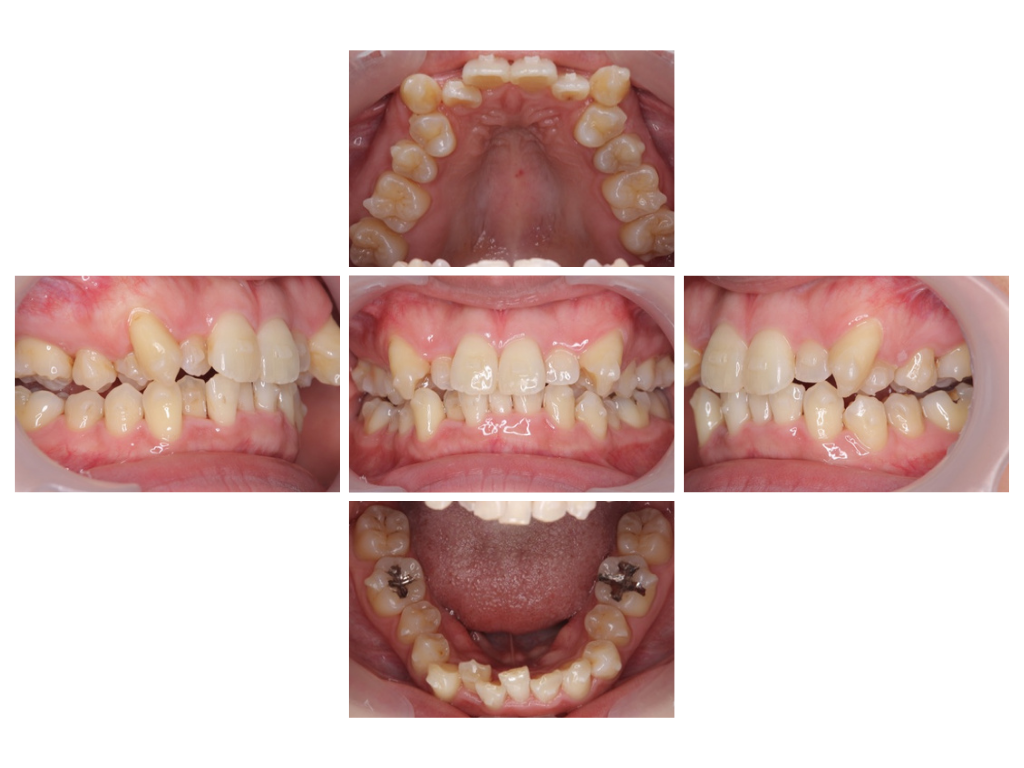

before

40代/女性 歯のガタガタが気になる

期間 ➖ 4年6か月

費用 ➖ 880,000円(税込・調整料込)

治療内容 ➖ 歯並びがデコボコしていたため、顎の横幅を広げてスペースを作り、きれいに並べました。

前歯が前に出ないように、噛み合わせのバランスを整えながら治療を進め、上下の真ん中の位置(正中)も揃えました。